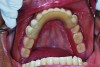

Maxillary RPD framework and anterior teeth patterns were produced using rapid prototyping 3D resin printing. Remaining parts of the overlay removable partial overdenture were waxed conventionally.

The wax pattern was invested, and the protocol for the fabrication of DuraCetal thermoplastic RPD framework was followed, utilizing the FlexPressTM Automated Digital Injection System (Myerson DuraCetal, www.duracetal.com) by Drake Precision Dental Laboratory. The removable partial overdenture was divested, finished, and polished using regular procedures (Figure 16).

The overlay partial was seated clinically, and minor adjustments were made to allow for full seating and occlusal equilibration centric and eccentric positions (Figure 17).

The interim overlay RPD in this situation was used to determine if the patient would tolerate the proposed change in OVD and if improved esthetics and orientation of the plane of occlusion would result. This critical information was used to formulate an acceptable definitive treatment plan to address the patient’s esthetic and functional needs. The definitive treatment plan may include implants, fixed prosthodontics, removable prosthodontics, or a combination of these therapies.

Fig 17. Completed maxillary overlay acetal resin removable partial overdenture.